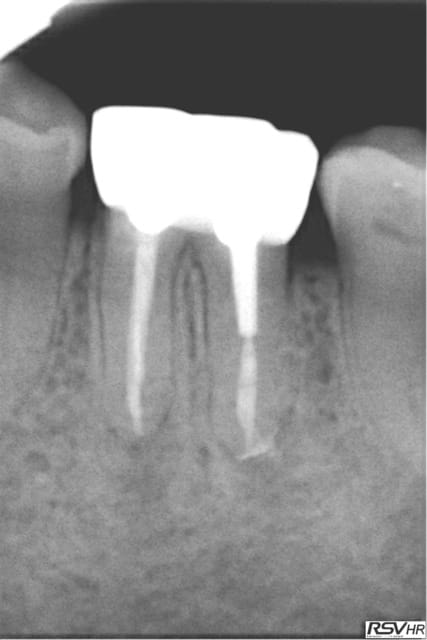

Tu peux me faire un CBCT de 35 ? Il semble y avoir un 4ième bien que le tt endo soit correct.

Je viens de faire une bio sur 45 (pulpite). Et je crois que j'ai ma petite idée sur la cause du 4 ième de 35. -)

Capture d e cran 2016 02 10 10.04 - Eugenol

Capture d e cran 2016 02 10 10.05 - Eugenol